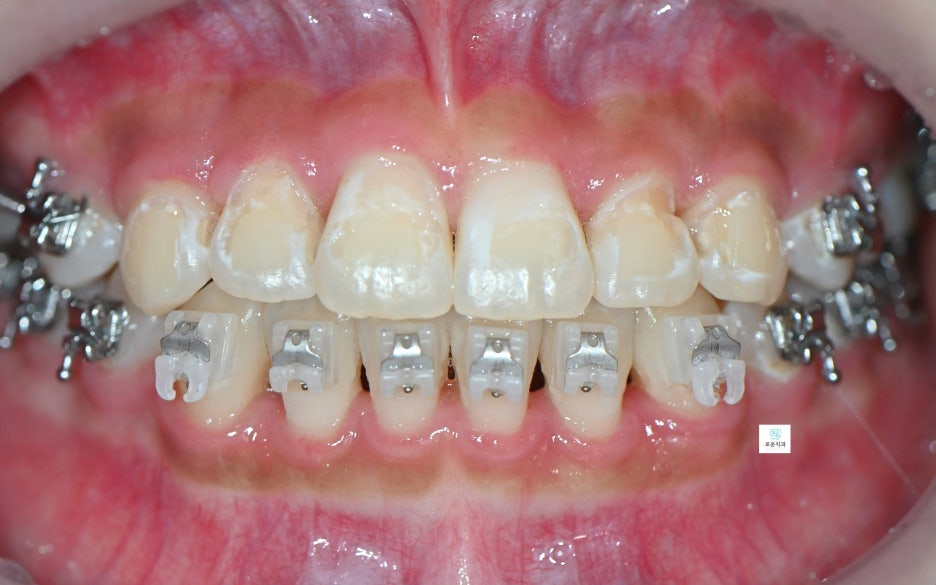

자연스럽고 깔끔하게 마무리된

앞니 치료 결과를 확인할 수 있습니다.